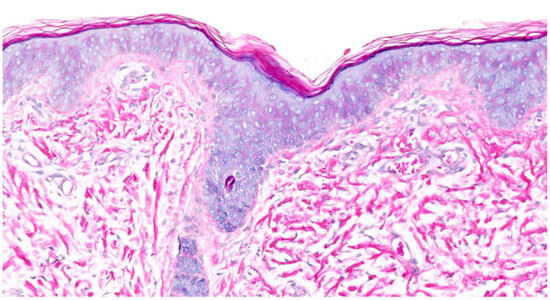

Inflammatory skin diseases are characterized by complex interactions between immune pathways, epidermal barrier function, and environmental triggers, leading to distinct clinical and histopathological features. This narrative review aims to integrate current knowledge on the cutaneous immune microenvironment across major inflammatory skin diseases, including

Inflammatory skin diseases are characterized by complex interactions between immune pathways, epidermal barrier function, and environmental triggers, leading to distinct clinical and histopathological features. This narrative review aims to integrate current knowledge on the cutaneous immune microenvironment across major inflammatory skin diseases, including atopic dermatitis, psoriasis, hidradenitis suppurativa, and vitiligo. A comprehensive literature search was conducted using PubMed, Web of Science, and Scopus, focusing on studies published between 2021 and early 2026. The findings highlight disease-specific immune signatures, such as Th2-driven inflammation in atopic dermatitis, IL-23/Th17 axis activation in psoriasis, neutrophil-dominated responses in hidradenitis suppurativa, and cytotoxic T-cell-mediated melanocyte destruction in vitiligo. These molecular pathways are closely reflected in histopathological patterns, emphasizing the link between morphology and immunopathogenesis. Advances in targeted therapies, including biologics and Janus kinase inhibitors, demonstrate the clinical relevance of these pathways and support a transition toward mechanism-based treatment strategies. Dermatopathology is increasingly contributing to precision medicine approaches by supporting correlations between tissue features, immune pathways, and potential therapeutic targets. This review provides a framework for improved disease stratification and for the development of personalized treatment strategies in inflammatory skin diseases.